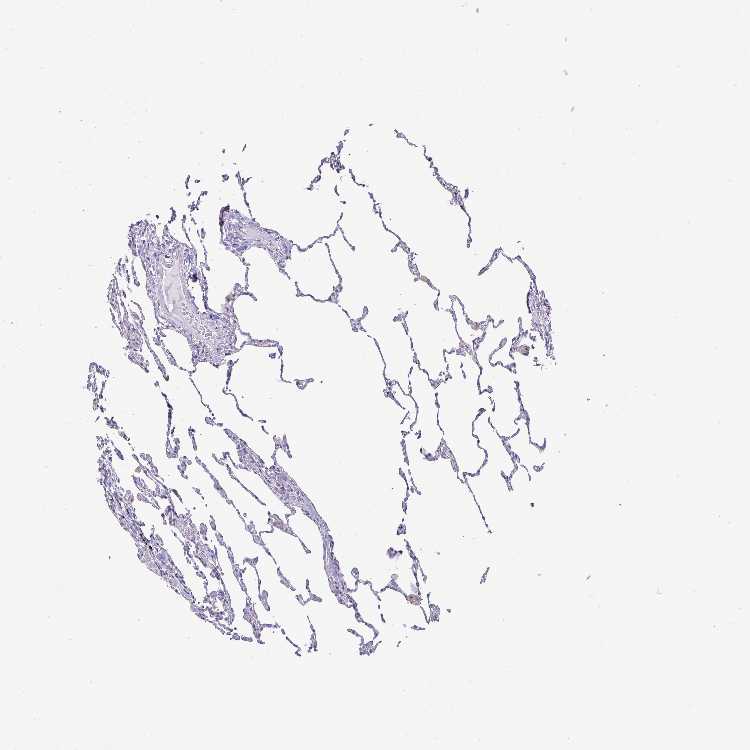

LUNG - Antibody stainingi

Antibody staining in the annotated cell types in the current human tissue is reported as not detected, low, medium, or high, based on conventional immunohistochemistry profiling in selected tissues. This score is based on the combination of the staining intensity and fraction of stained cells.

Each image is clickable and will lead to virtual microscopy that enables deeper exploration of all samples and also displays staining intensity scores, fraction scores and subcellular localization as well as patient and tissue information for each sample.

Antibody HPA054437Antibody HPA058511Antibody CAB002776Antibody CAB015122

Alveolar cells Not detectedNot detected-Not detected

Alveolar cells type I --Not detected-

Alveolar cells type II --Not detected-

Endothelial cells --Not detected-

Macrophages LowLowMediumMedium